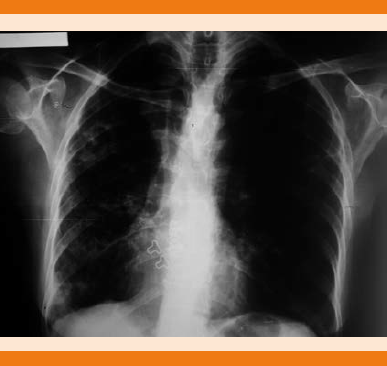

Inició en junio de 2008 con tos productiva, esputo blanquecino, acompañado de hemoptoicos escasos, en accesos, no disneizante ni emetizante, sin fiebre, sin pérdida de peso, se diagnosticó de manera inicial como bronquitis aguda, por lo que se administró tratamiento antibiótico con betalactámicos, sin remisión de los síntomas; al considerar la exposición a humo de biomasa se diagnosticó clínicamente enfermedad pulmonar obstructiva crónica, se inició tratamiento con agonistas beta 2 adrenérgicos de acción prolongada con esteroide inhalado, salmeterol 50 µg/fluticasona 100 µg, dos inhalaciones cada 12 horas y anticolinérgicos de acción prolongada, tiotropio cápsulas de 18 µg, una inhalación al día. Se mantuvo en control durante tres años, sin ningún episodio de exacerbación que requiriera hospitalización pero con persistencia de síndrome tusígeno crónico, reinició con hemoptoicos en 2011, que eran esporádicos con exacerbación relacionada con cambios de clima, por lo que se solicitaron baciloscopias en esputo seriadas que resultaron positivas ++/+++ y radiografía de tórax (Figura 1); se estableció diagnóstico de tuberculosis pulmonar, se inició tratamiento de seis meses con Dotbal® (rifampicina 150 mg/isoniazida 75 mg/pirazinamida 400 mg/etambutol 300 mg) en fase intensiva y de sostén. Por persistencia de tos, pérdida de peso y baciloscopias positivas +++ en 2012 se dio tratamiento durante dos años, considerando recaída de tuberculosis pulmonar, con baciloscopias positivas + y ++, en algunas ocasiones negativas, con reajustes intermitentes del esquema antituberculoso, se valoró por los servicios de Neumología e Infectología, se solicitó tomografía torácica (Figura 2) y cultivo de expectoración, como lo marcan los lineamientos nacionales, gestionado por el Laboratorio Estatal de Salud Pública de Tamaulipas y el Instituto de Diagnóstico y Referencia Epidemiológicos (InDRE), con desarrollo de Mycobacterium abscessus en dos muestras separadas y que, aunado al cuadro clínico, se estableció el diagnóstico de micobacteriosis pulmonar secundaria a Mycobacterium abscessus, por lo que se decidió inicio de tratamiento en noviembre de 2014 con amikacina 500 mg intramuscular c/24 horas durante dos meses más claritromicina 500 mg c/12 horas de manera indefinida, por no ser apta para resección de la lesión por afección bilateral no se envió a valoración de cirugía cardiotorácica.

Figura 2 Tomografía simple de tórax en la ventana pulmonar donde se observa patrón nodular bilateral, de predominio derecho, fibrosis, bronquiectasias y cavitación.